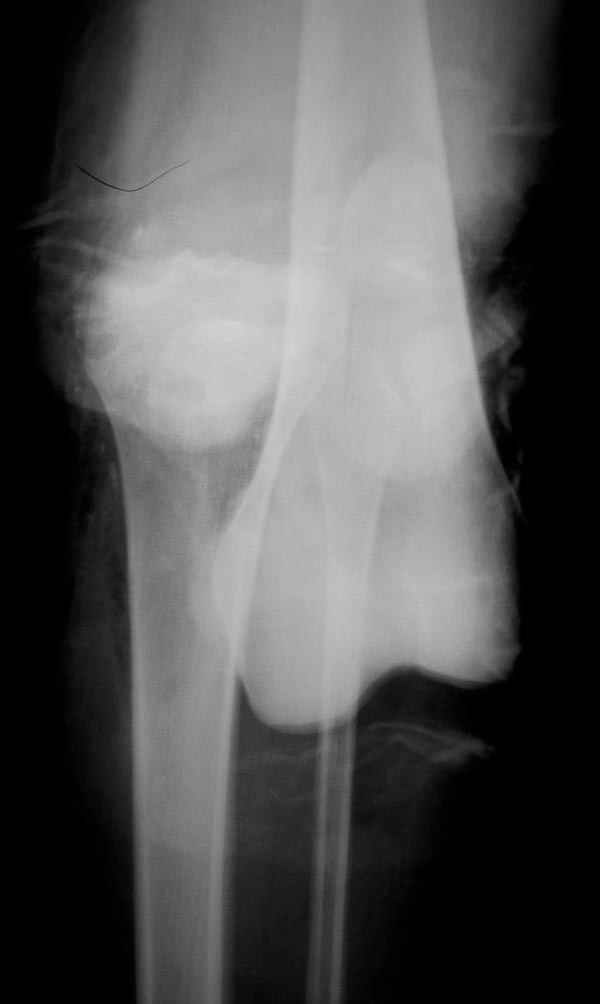

В приемное отделение поступает больная 22 лет, во время аварии ремень безопасности не был пристегнут, в крови большое количество кокаина.В приемном срочная интубация и седация, сделаны снимки.Диагностирован: открытый вывих левого коленного сустава.

Заключительный диагноз: Открытый вывих коленного сустава, перелом надколенника, разрыв собственной связки надколенника